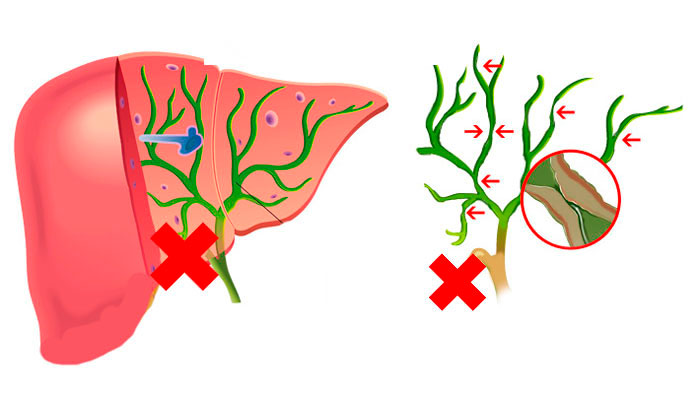

Фотографии и изображения, связанные с симптомами первичного склерозирующего холангита